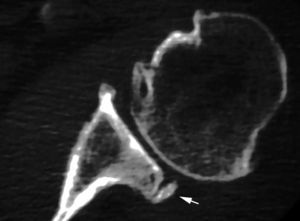

Esta lesión se produce a consecuencia de una tracción repetitiva de la unión cápsulo-perióstica posterior, produciéndose una osificación semejante a un espolón óseo (fig. 15).

Fig. 15.--Lesión de Bennett. Tomografía axial computarizada (TAC) axial (A) y resonancia magnética (RM) T1 axial (B) que revelan la presencia de un «espolón» óseo adyacente al borde glenoideo posterior (flechas en A y B). Nótese la ausencia de una lesión del labio glenoideo posterior en B.